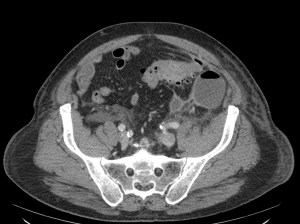

TC ABDOMEN: Se confirman los hallazgos vistos en ecografía. Se aprecia un engrosamiento mural > 4mm de un segmento aproximado de 5.5 cm de longitud con infiltración de la grasa adyacente y sin visualizar colecciones ni gas extraluminal, hallazgos compatibles con diverticulitis aguda no complicada.

CONCLUSIÓN: Diverticulitis aguda no complicada. HINCHEY grado 0